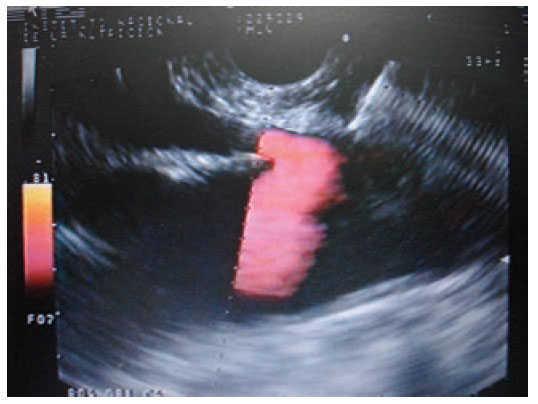

Materials and methodsIn a retrospective analysis of data obtained prospectively the records of patients with pain caused by pancreatic cancer who underwent EUS CPN at the Instituto Nacional de Ciencias Médicas y Nutrición “Salvador Zubirán” from March 2005 to May 2007 were evaluated. All patients have unresectable pancreatic cancer confirmed by computed tomography (CT), magnetic resonance imaging (MRI) and/or EUS; EUS criteria and fine-needle aspiration (FNA) were used when a tissue diagnosis was not available before EUS. They underwent to EUS CPN during the same EUS procedure for diagnosis. Before the procedure all patients had laboratory tests including prothrombin time and full blood count. The patients were placed in left decubitus position and sedated by using a combination of midazolam, propofol and phentanyl by anesthetist. Patients were continually monitored with an automated noninvasive blood pressure device, electrocardiogram, and pulse oximetry throughout the procedure. EUS CPN was performed with a linear array echoendoscope GFUCT-140 (Olympus) by an experienced echoendoscopist. The angle formed by the aorta and celiac trunk was identi- fied through the posterior gastric wall. Under direct EUS visualization, a 22 gauge, 8 cm aspiration needle (Wilson-Cook Medical, Inc. Winston-Salem, N.C.) primed with normal saline solution was placed immediately adjacent and anterior to the aorta at the level of the celiac trunk (figure 1). After injecting 2 mL of saline solution to clear the needle, an aspiration test was performed, if no blood was obtained, 10 mL of 1% lidocaine was injected (figure 2). The aspiration test was repeated, and if no blood, 20 mL of dehydrated 98% absolute alcohol was injected. The needle was then flushed with 3 mL of saline solution and withdrawn from the patient. After the procedure a Doppler ultrasound of the celiac trunk and aorta was made to evaluate permeability. The average estimated time for the EUS CPN portion of the procedure was 10 minutes. After the procedure all patients remained under observation for at least 2 hours to rule out any complications. All patients were reevaluated for complications 7 days after the procedure. Dosage and class of pharmacologic treatment were evaluated before the procedure as well as 15 days and 30 days after procedure. Measurement of intensity of pain was made with a validated visual analog pain scale (0-10) in all patients6 by a pain specialist. Measurements two and four weeks after the procedure were made. The complications related to the EUS CPN were determined in agreement with the medical records. Medians, ranges and proportions were used to summarize the demographics and clinical variables. EUS CPN pain scores paired before and after (15 and 30 days) were compared with the Friedman test.

Figure 1. Needle adjacent and anterior to the aorta at the level of the celiac trunk.